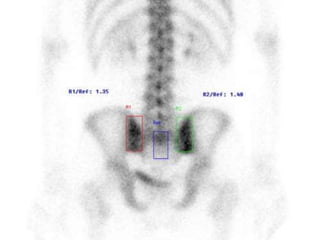

Sacroiliitis

 30 year old man with LBP HLAB27+

Synovitis, subchondral edema, iliac side more common